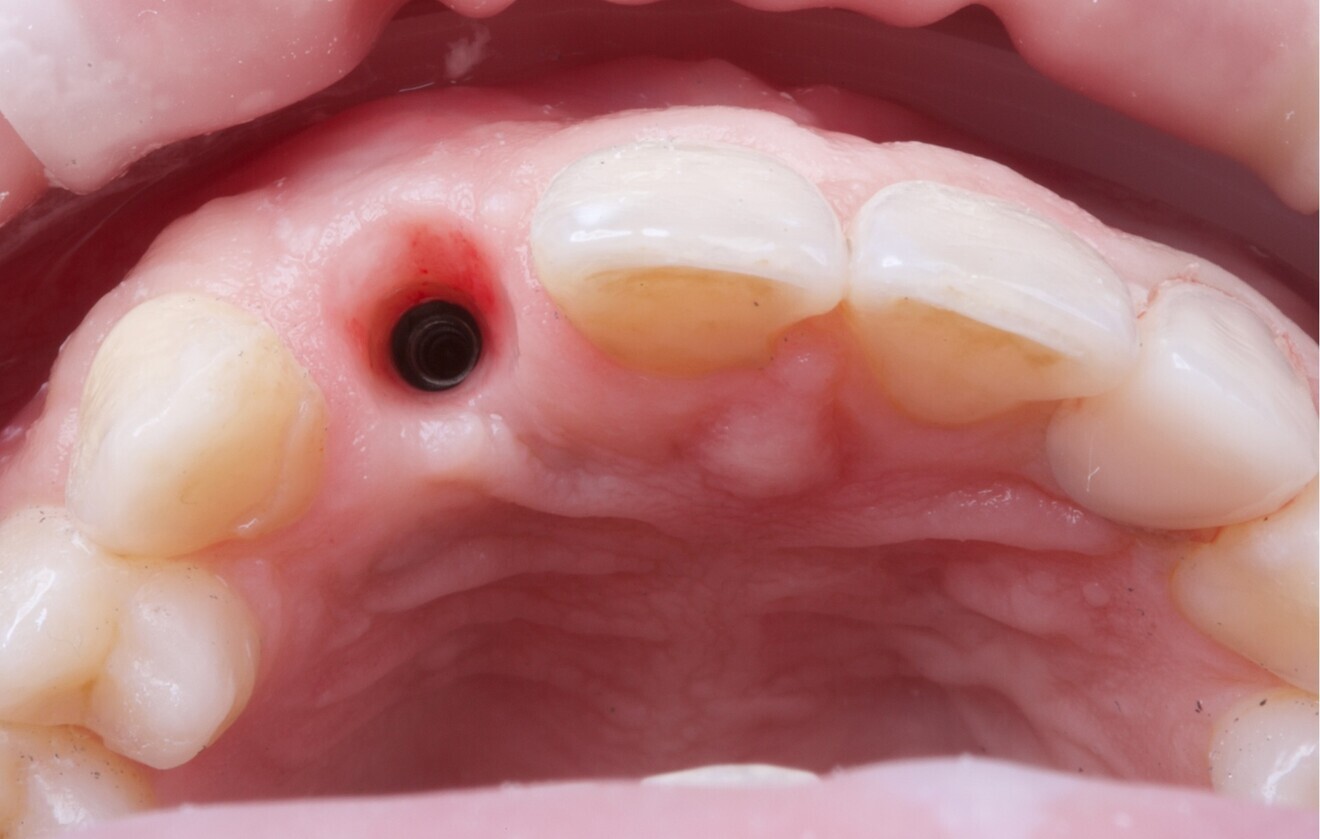

Fig. 2: CBCT evidence of labial implant malposition and bone loss.

Periapical radiographs showed bone contact on the mesial and distal aspects of the implant. However, clinical probing and CBCT revealed labial and palatal bone loss, consistent with a labially malpositioned implant (Fig. 2).